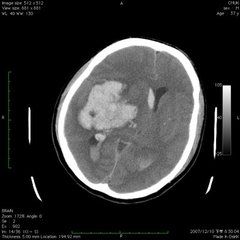

腦室內出血(一)早期腦內出血:也叫原發性腦內出血,指外傷後即刻或不久發生的出血,比較常見。因暴力的直接作用導致腦組織及血管同時損傷,或腦組織內血管單獨損傷所引起。其出血範圍常較大,單發或多發,有占位效應。如動脈出血,則出血範圍較靜脈出血時廣泛。有時在大片出血的周圍可見點狀出血,多是由於暴力作用引起局部血液循環紊亂而發生,常在傷後一段時間才出現。大片出血發生的部位多為暴力作用衝擊的部位,如暴力作用局部的大腦皮質下層的白質、基底節和腦幹。對沖性腦內出血可能程度更重,傷者多有明顯的顱內高壓症狀和體徵。如出血發生在腦幹,則傷後持續性深度昏迷。如果出血範圍較大或位於腦幹,死亡率常較高且發生較快。死因常為腦幹損傷出血、腦疝形成。這種出血即使經過手術治療,死亡率也較高。腦內出血經頭部CT掃描,在腦實質內發現局灶性高密度影即能診斷。較小的腦內血腫經過一周左右多可被液化、吸收,或機化形成瘢痕。較大的血腫如沒有很快死亡,一般在傷後2~3周內纖維包裹,血凝塊可液化,而成為囊腫。囊腫壁和瘢痕處因含吞噬含鐵血黃素的巨噬細胞而呈棕黃色,說明是因出血而非腦軟化的結果。小的點狀出血多數可完全吸收而不留痕跡。腦內血腫如較大,有時可破入鄰近的蛛網膜下腔或腦室。